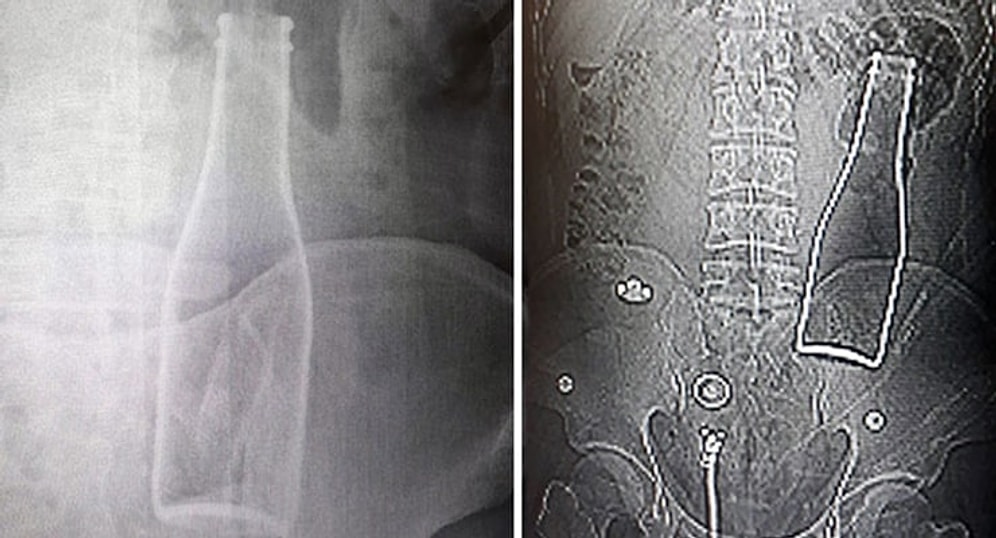

Vücudundan Soda Şişesi Çıkan Genç: 'Yanlışlıkla Oldu'

Karaman’da karın ağrısı şikayetiyle gittiği hastanede çekilen röntgen filminde kalın bağırsağında şişe olduğu ortaya çıkan Afgan A.E.'nin (27) ifadesinde, ''Olay günü banyoda duş alırken yanlışlıkla bu olay gerçekleşti'' dediği ortaya çıktı.